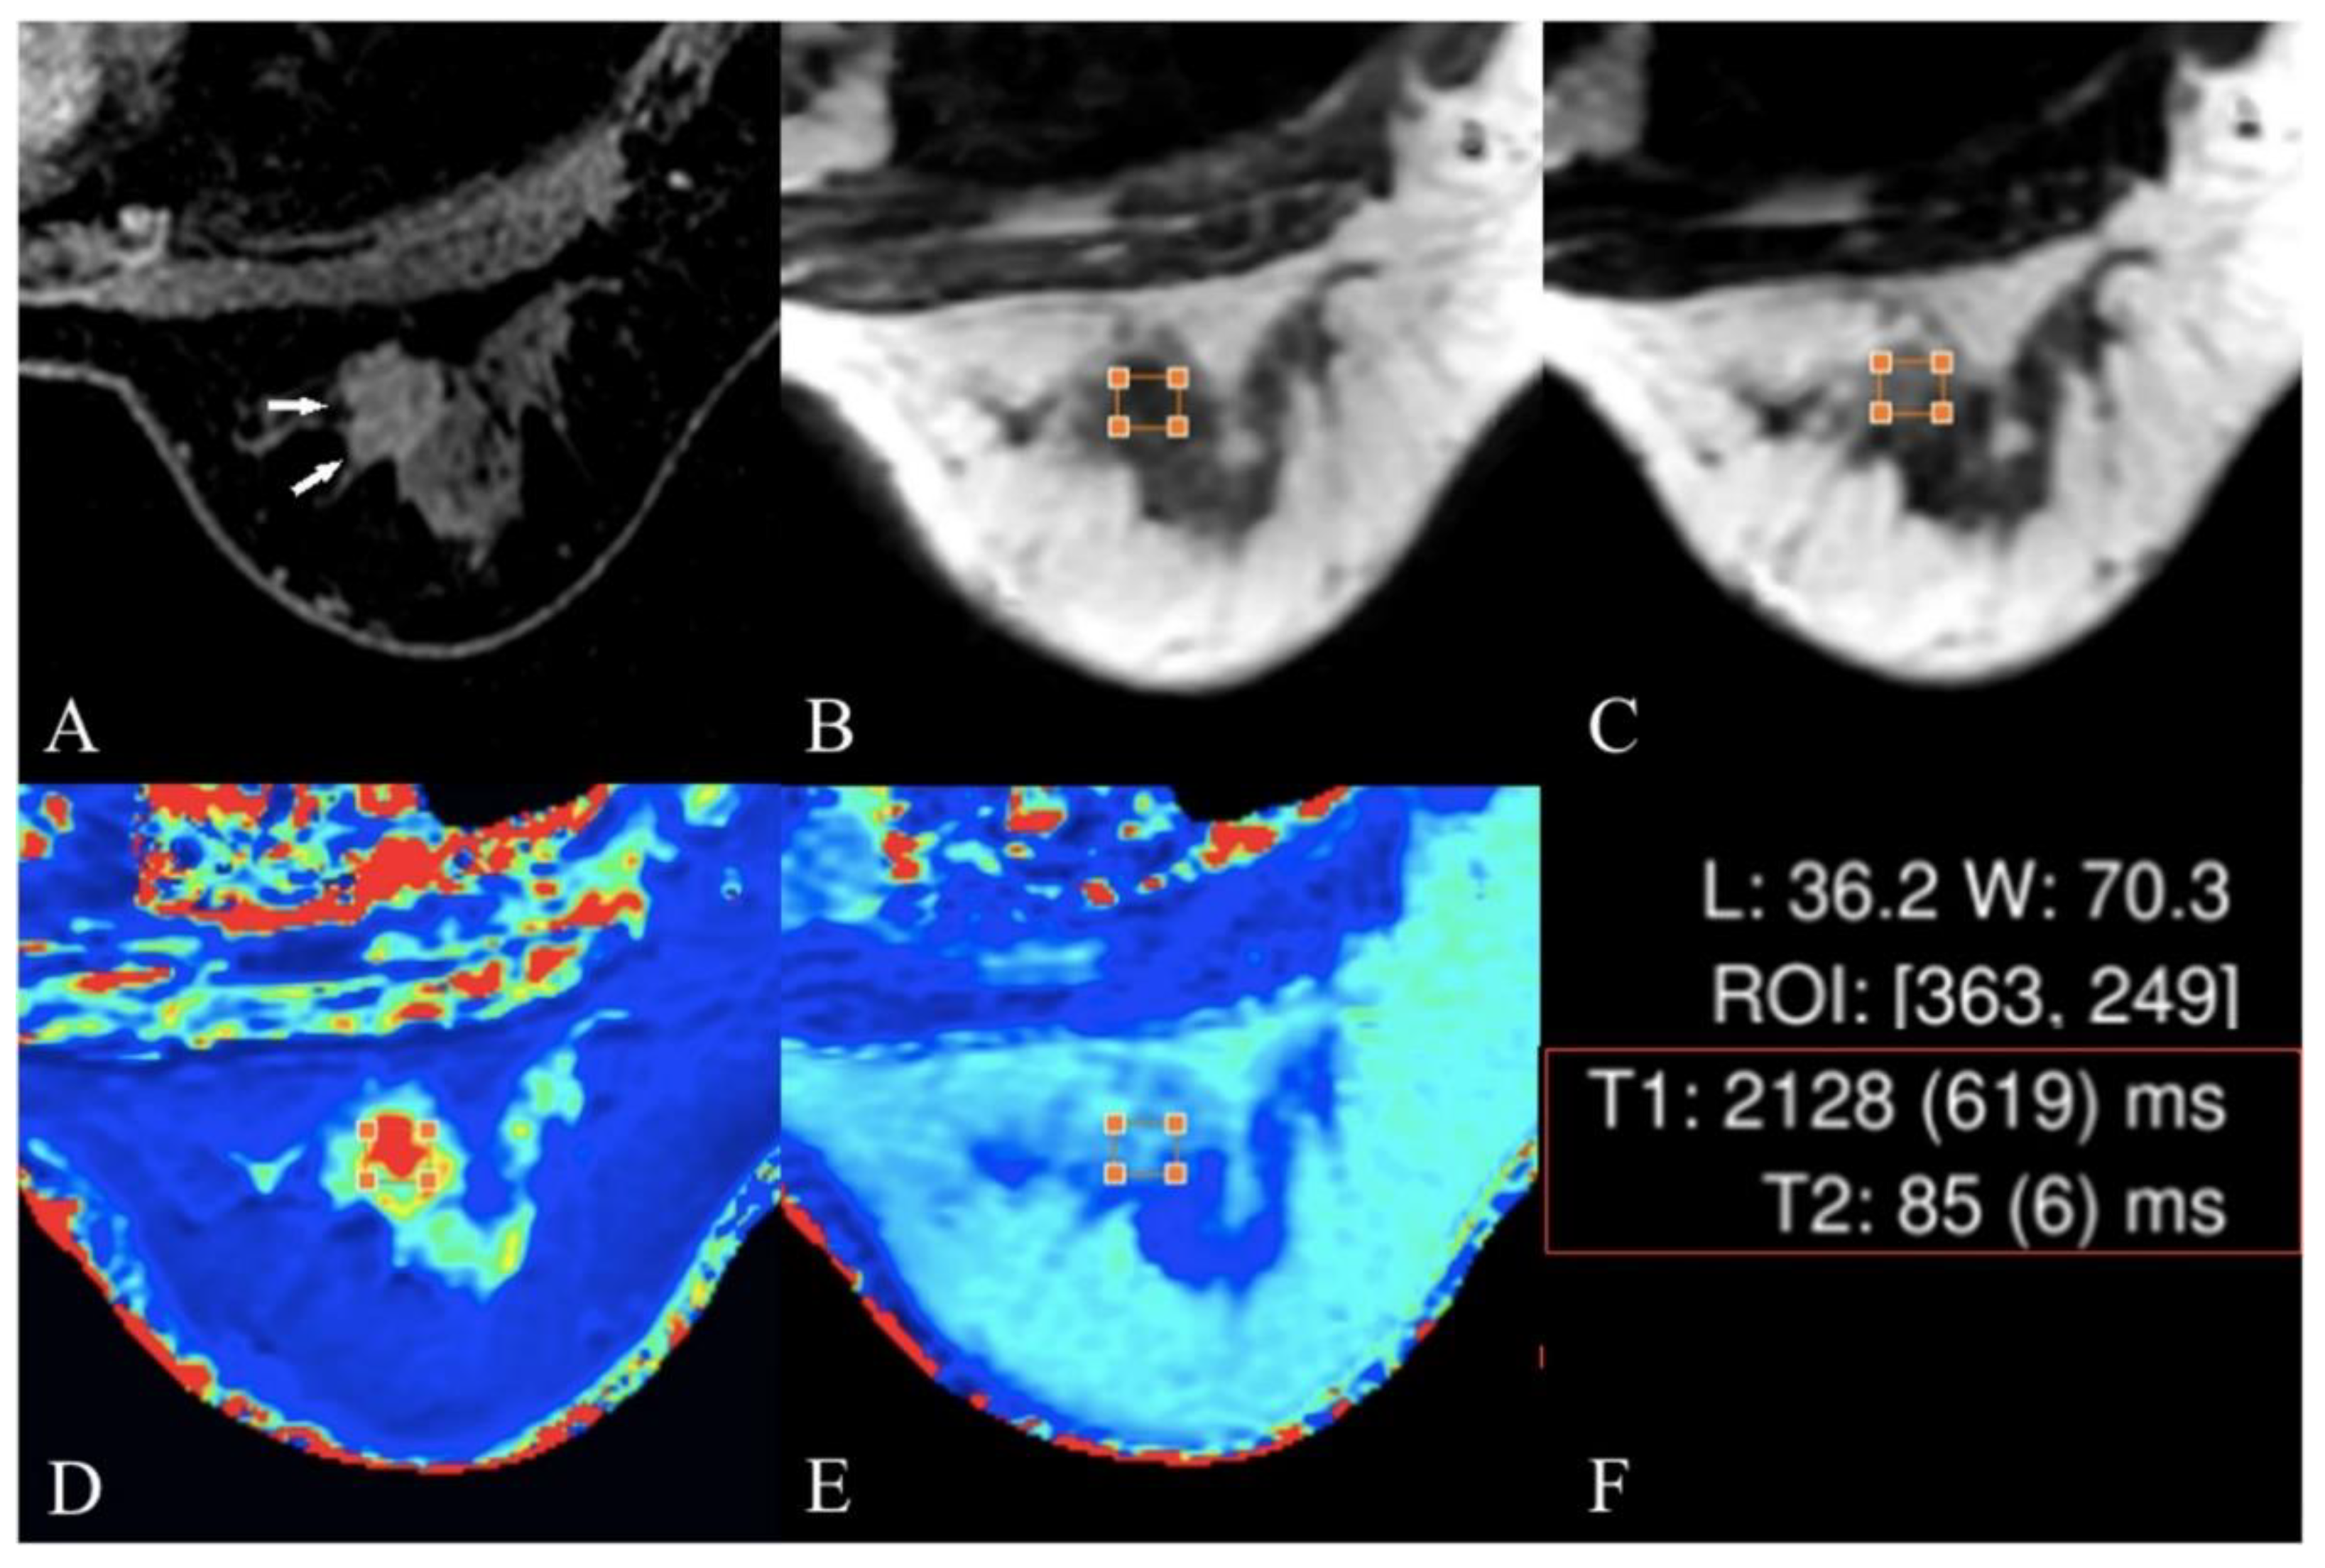

4.5. T2 and T2* Mapping

- Meng, T.; He, N.; He, H.; Liu, K.; Ke, L.; Liu, H.; Zhong, L.; Huang, C.; Yang, A.; Zhou, C. The diagnostic performance of quantitative mapping in breast cancer patients: A preliminary study using synthetic MRI. Cancer Imaging 2020, 20, 88. [Google Scholar] [CrossRef] [PubMed]